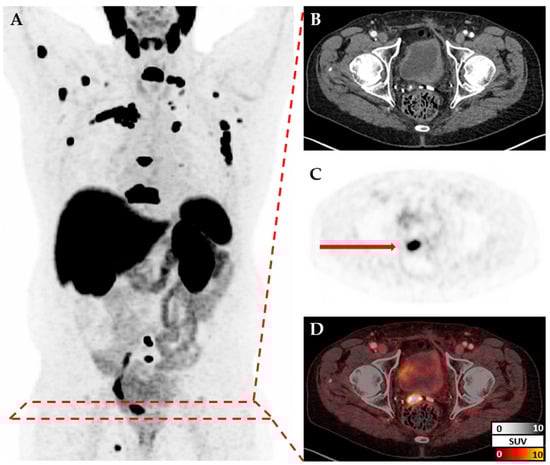

2.2. Data Processing

Images were exported from the clinic PACS in DICOM format and converted to NIfTI via dcm2niix [12]. These NIfTIs contain intensities in Becquerels/milliliter (BQML) in order to convert them to standardized uptake calue (SUV), and scan-specific scaling factors were calculated from DICOM metadata. Data loaders for deep learning in Python (version 3.12.3) were implemented using nibabel (version 5.2.1, [13]), PyTorch (version 2.3.0, [14]), and Monai (version 1.3.1, [15]). CT and PET images for each patient were measured at different resolutions but co-registered to a common space to ensure accurate spatial alignment (Figure 1). Therefore, after reading both files individually, they were re-scaled to a matrix size of 150 × 150 × 150. Depending on the pixel spacing and slice thickness of the original scans, the resulting voxel size differed between patients. Intensity was re-scaled to a range of 0 to 1 based on the minimum and maximum values in each scan. Models with consistent scaling across scans using a fixed linear transformation were explored (Appendix A). Additional transformations like cropping or augmentation transformations were applied depending on the model. Metadata and labels were provided as a simple csv file and loaded via Pandas (version 2.2.2, [16,17]).

Appendix A.2.2. Uncropped NIfTIs (Model 1)

In Model 1, uncropped NIfTIs were used. These show the patient from the thigh to the head and therefore contain a lot of information that is not part of the objective of this work. One of these uncropped NIfTIs with computed tomography (CT) channel and positron emission tomography (PET) channel can be seen in Figure 1 in the main text.